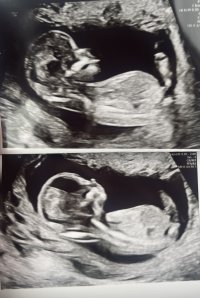

100% gutt12+2 i dag. Hvilket kjønn tror dere?

Vis vedlegget 456403

Det så veldig ut som en gutt![]()